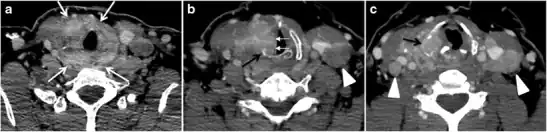

Fig. 6. A 61-year-old female patient with locally aggressive PTC. an Enhanced axial CT scan of the neck demonstrates a heterogeneous infiltrative thyroid mass. This mass diffusely involves the entire gland and circumferentially encases the trachea with involvement of bilateral tracheoesophageal grooves (white arrows). b, c Additional axial cranial images show right cricoid cartilage destruction (black arrows in b), right thyroid cartilage destruction (black arrow in c), right vocal cord paralysis (white arrows in b), and bilateral cervical lymphadenopathy (arrowheads).[1]